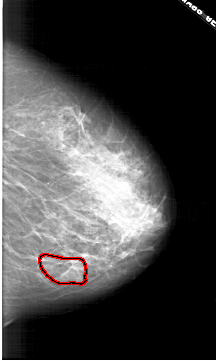

A_1771_1.RIGHT_CC

RIGHT_CC LINES 5761 PIXELS_PER_LINE 3451 BITS_PER_PIXEL 12 RESOLUTION 43.5 OVERLAY

FILE: A_1771_1.RIGHT_CC.OVERLAY

TOTAL_ABNORMALITIES 1

ABNORMALITY 1

LESION_TYPE MASS SHAPE LOBULATED MARGINS ILL_DEFINED

ASSESSMENT 4

SUBTLETY 3

PATHOLOGY BENIGN

TOTAL_OUTLINES 1

BOUNDARY